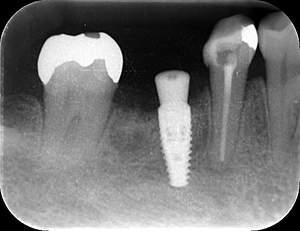

インプラント治療の症例2

レントゲン写真

- Befor

- After

| 年齢 | 50代・男性 |

| 主訴 | 左上7番 左下5番7番 |

| 治療内容 | ・インプラント埋入 ※1:GBR(骨造成)・・・骨再生誘導法。骨の高さや厚みを人工骨や人工膜などを使用し再生する方法 |

| 治療費 | 合計:1,809,500円(税込) ■内訳 ・左上7番 ・左下5番7番 |

| 治療期間 | 左上7番約1年 左下5番7番約10ヵ月 |

| 治療方針 | 左上7番は昔他院で被せものをしており、被せものの中が歯ぐきの中まで虫歯になっていたため抜歯せざるを得ない状態だった。抜歯と同時に骨造成を行い、骨が出来るまで4ヵ月待ってからインプラントを埋入した。 ※2ポンティック・・・歯のない部分を補うダミーの歯。 |

| 担当者所見 | 元々金属の被せものが多く入っていたため、2次カリエス※3が多かった。今回は金属ではなく、ジルコニアを使用し、2次カリエスにならないよう、患者様にはブラッシング指導とメンテナンスの重要性をお伝えした。 ※3二次カリエス・・・詰め物や被せものを入れた歯が虫歯になること。 |